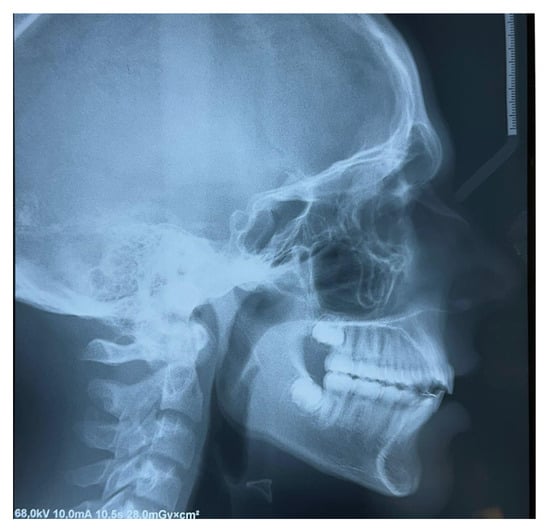

Lateral teleradiography confirmed the skeletal Class II Division I type malocclusion with a mandibular retrusion (Figure 4).

Figure 4.

Lateral teleradiography at T0.